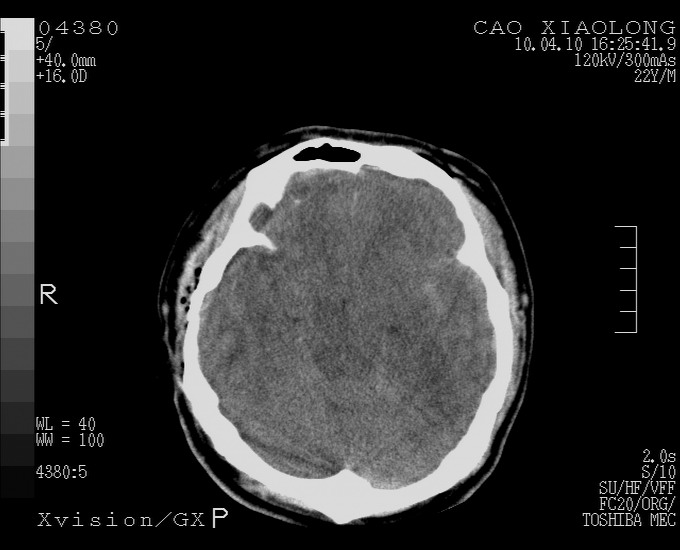

以下是引用随光逐影在2010-4-11 11:00:00的发言:[br]1)左侧额颞顶部硬膜下血肿。2)蛛网膜下腔出血。3)右侧颞顶部颅骨线形骨折。[br][br]20小时后复查:左侧额颞叶脑挫裂伤;左侧额颞顶部硬膜下血肿及蛛网膜下腔出血有吸收表现;右侧颞顶部颅骨线形骨折。[br]